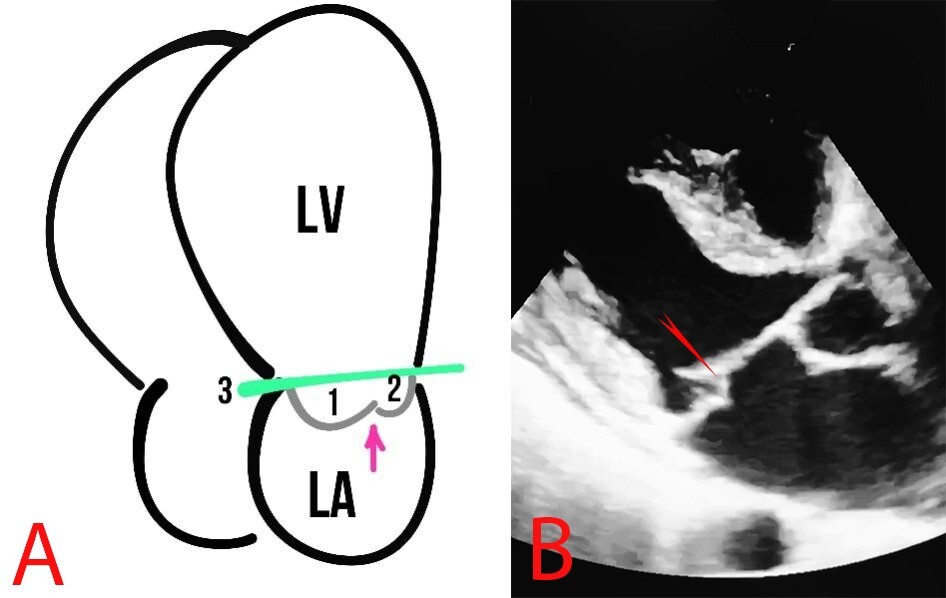

MVP is defined as the billowing or bulging of MV leaflets more than 2 mm above the mitral annulus in a long-axis view (Fig. 4).

Fig. 4. MVP. (A) Schematic presentation of MVP. The arrows show the MV, 1 and 2 represent the MV leaflets, the line (3) shows the mitral annulus, and the arrow depicts the coaptation zone. (B) Echocardiography of a patient with MVP, the red arrow indicates MVP.